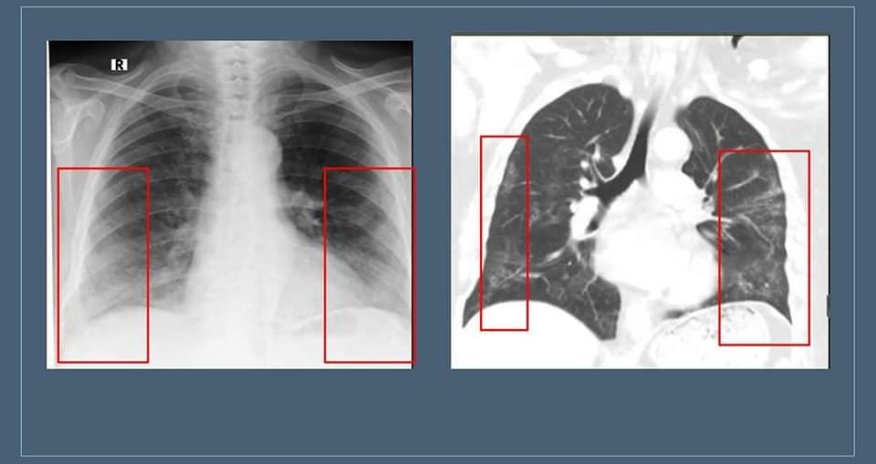

Həkimin sözlərinə görə, bəzən normal hallarda da "buzlu şüşə” görüntüsü radioloji görüntülərdə izlənilə bilər: "Məsələn, müayinə zamanı xəstə dərindən nəfəs almazsa və ya müayinə nəfəsvermədə aparılarsa, ağciyərin havalılığının fizioloji ekspirator zəifləməsi səbəbindən bütün ağciyər sahələri homogen olmaqla "buzlu şüşə” görüntüsü verə bilər. Hazırda "buzlu şüşə” görüntüsü koronavirus pnevmoniyasının əsas radiodiaqnostik əlaməti hesab edilir. Bu o deməkdir ki, normalda şəffaf havalı görünən ağciyərdə belə hallarda yarımşəffaf zonalar izlənilir, ağciyər sanki dumanlı görünür. Bu zaman bronx strukturlarının və pulmonar damarların saxlanması ilə ağciyərlərin eksudat və ya transudatla tutulması, interstisial qalınlaşmalar və ağciyər alveollarının hissəvi kollapsı ilə müşahidə olunan görüntü meydana çıxır. Buzlu şüşə xəstəliyin 3-4 günlərindən inkişaf etməyə başlayır və xəstə sağaldıqdan hətta bir ay sonra belə qala bilir. Xəstəliyin yüngül və orta ağır dərəcəsini keçirmiş xəstələrdə 2-3 aydan sonra dəyişikliklər tamamilə itir”.